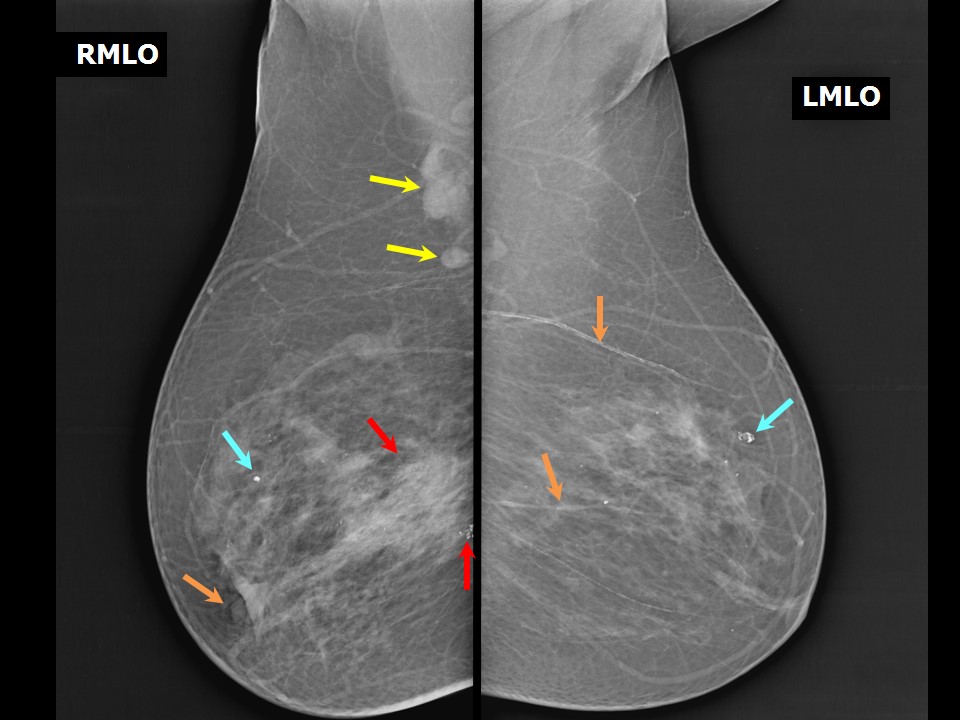

Феномен гипердиагностики в маммографии: примеры и иллюстрации

Раздел: Образы вокруг